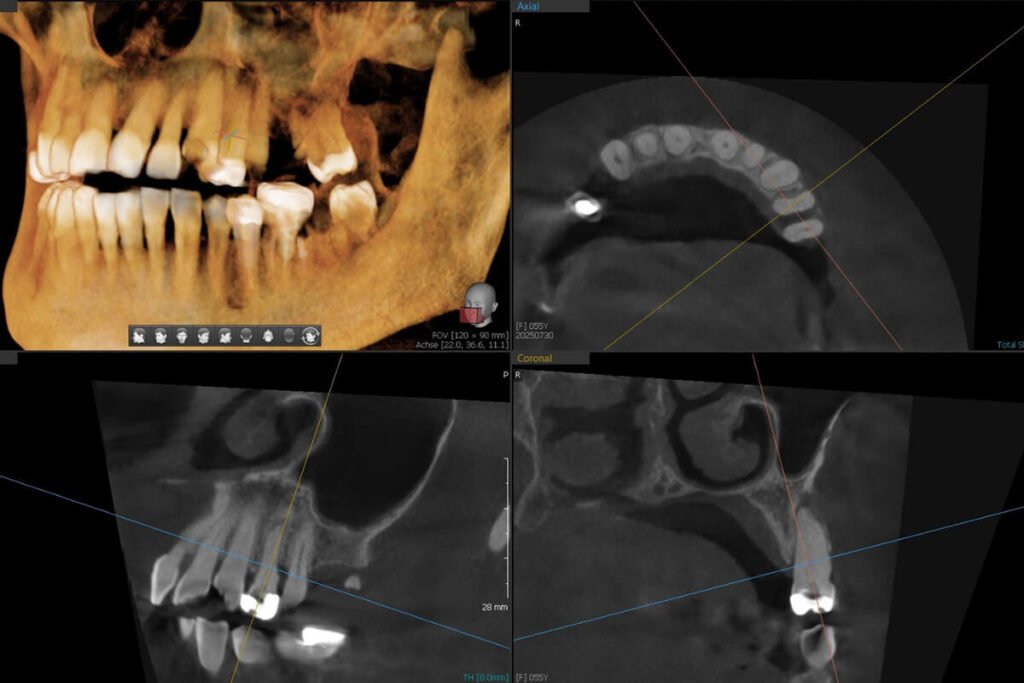

• Digitale Volumentomographie (DVT): modernste Methode, die ein dreidimensionales Bild liefert.